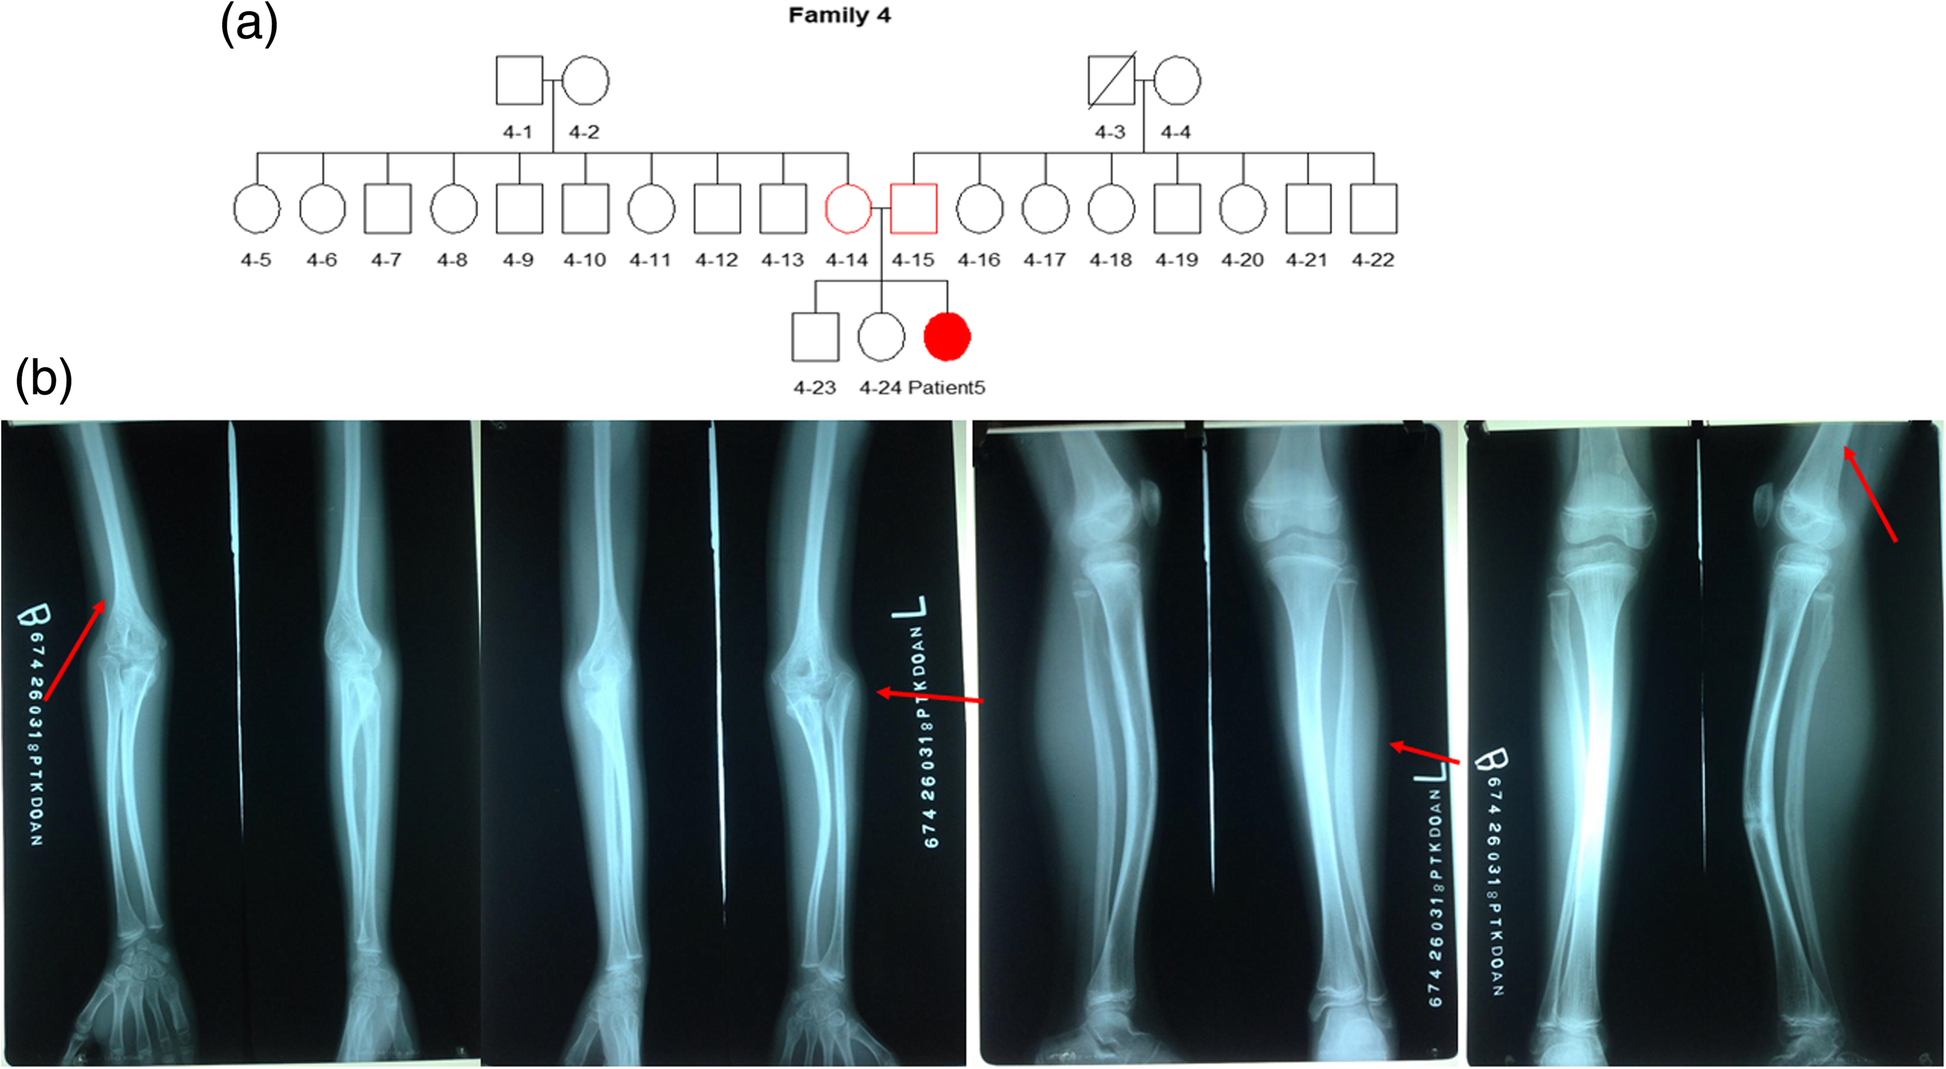

Fig. 5From: IFITM5 pathogenic variant causes osteogenesis imperfecta V with various phenotype severity in Ukrainian and Vietnamese patientsPatient 5. a Genealogical tree of patient 5 (family 4). b Radiological features of patient 5Back to article page